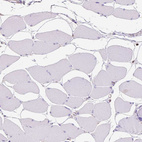

Immunohistochemistry analysis in human tonsil and skeletal muscle tissues using HPA070455 antibody. Corresponding INPP5D RNA-seq data are presented for the same tissues.